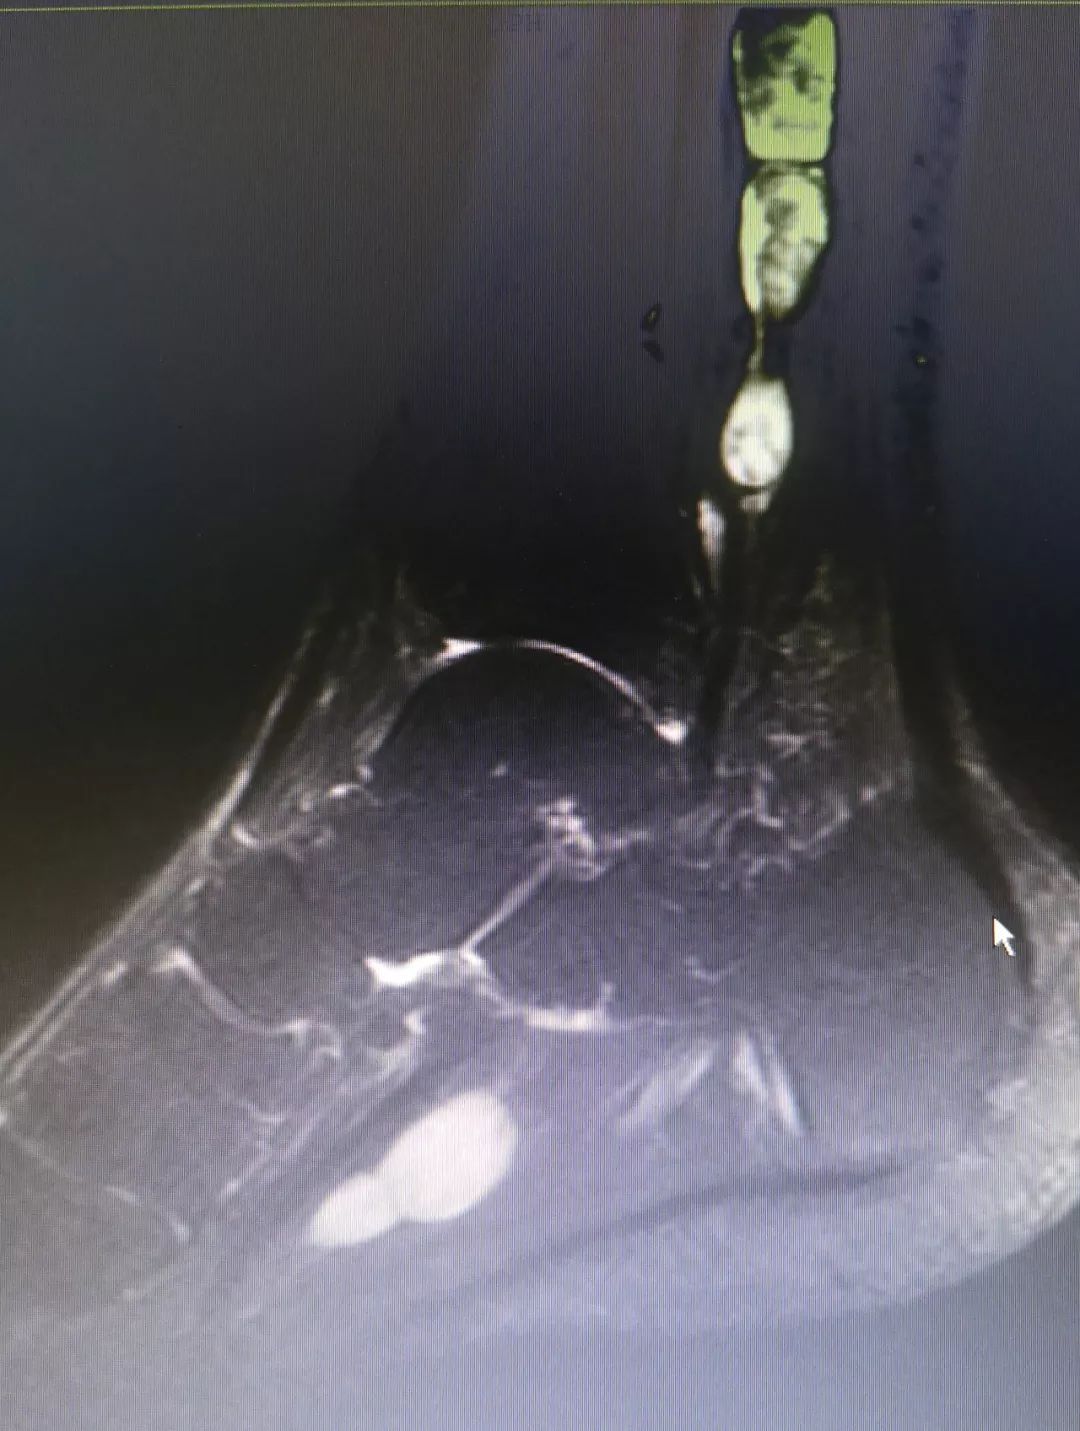

患者核磁共振片

在陈铿教授精心主刀和靳松教授配合下,患者的肿瘤慢慢被完整剥离,结果像羊肉串样,正常神经没有丝毫损伤。手术第二天,患者就下地活动,效果令人非常满意。随后,病理结果出来:不是神经纤维瘤,而是神经鞘瘤。